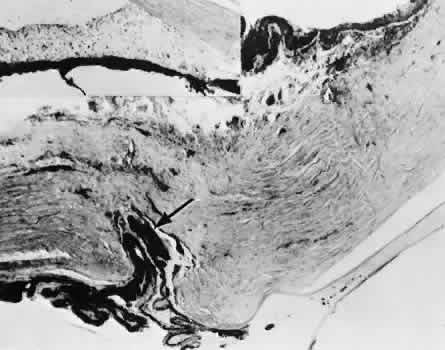

SCLERAL HEALING

The sclera itself does not participate directly in wound healing. Partial-thickness injuries are healed by formation of granulation tissue from the epi-scleral tissue in external wounds or from uveal tissue in internal wounds (Fig. 8). Full-thickness defects of the sclera heal by granulation tissue originating in the episcleral tissue and uveal tract. Mitomycin is used in filtering procedures specifically to prevent the formation of granulation tissue and promote establishment of an aqueous fistula.30

Fig. 8. Following a scleral incision, granulation tissue from episcleral tissue (E) and uveal tissue (U) will proliferate through the full extent of the sclera. The tissue will remodel along tension lines to reapproximate the tensile strength of the original tissue (Hematoxylin-eosin stain; × 28.)